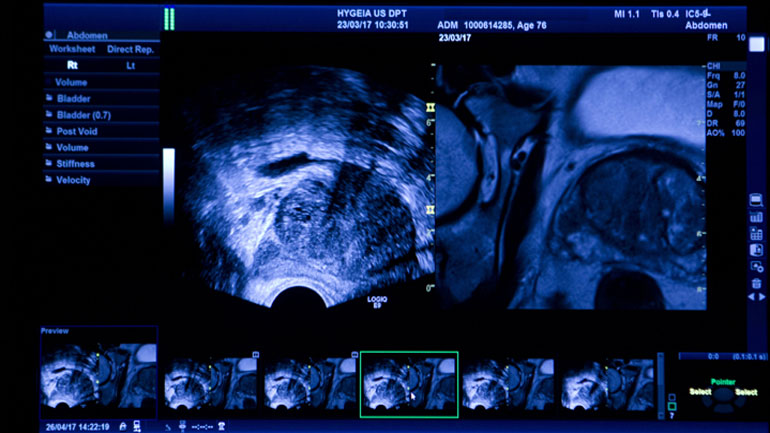

Πρωτοποριακό Σύστημα Υβριδικής Απεικόνισης για τον καρκίνο του προστάτη: Μέγιστη διαγνωστική ακρίβεια και ασφάλεια

Υψηλού επιπέδου διαγνωστικές υπηρεσίες υγείας για τον καρκίνο του προστάτη εξασφαλίζει το πρωτοποριακό Σύστημα Υβριδικής Απεικόνισης (Fusion Imaging)...